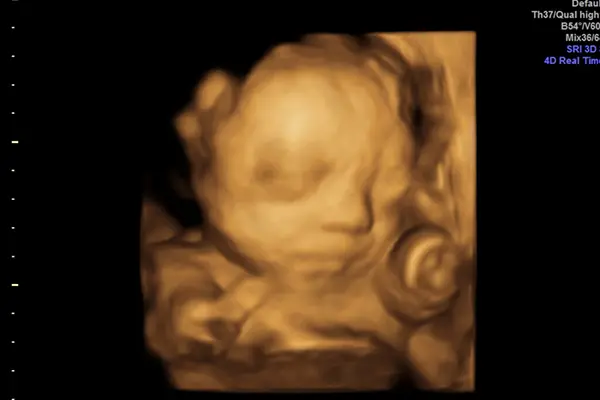

3D-/4D-Ultraschall bietet werdenden Eltern detaillierte und bewegte Bilder ihres Ungeborenen, um Entwicklungen besser zu verstehen.

Anhand der 3D-Sonographie können bereits im 2D-Ultraschall aufgefallene körperliche Besonderheiten (z. B. Gesichts-Spalten, Neuralrohrfehlbildungen wie eine Spina bifida) oft deutlicher gesehen und dementsprechend oft in ihrer Ausprägung und Behandelbarkeit besser eingeschätzt werden. Optimale Zeitpunkte für die Untersuchung liegen zwischen der 13.-16. SSW und zwischen der 26.-33. SSW, wobei noch andere Faktoren wie die Kindslage, die Fruchtwassermenge und auch die Stärke der mütterlichen Bauchdecke eine Rolle spielen.

Wird der 3D-Ultraschall um noch die weitere Dimension Zeit erweitert, spricht man vom 4D-Ultraschall. Damit lässt sich das ungeborene Baby in Bewegung darstellen.